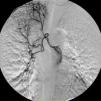

On the seventh day, a new episode of massive hemoptysis took place. On this occasion, the patient was hemodynamically unstable and the laboratory tests disclosed a hemoglobin of 7.3 g/dL. Two units of “packed” red blood cells and sufficient volume of crystalloid fluid were administered. The patient refused another bronchoscopy. Urgent bronchial arteriography was performed. Selective catheterisation of the right intercostobronchial trunk showed features of marked hypervascularization, including a tortuous and dilated right bronchial artery and bronchial-to-pulmonary retrograde shunts in the right apex (Figure 1). Selective catheterisation of the left bronchial artery showed a bronchovascular fistula, where contrast leaked from the blood vessel drawing the left bronchial tree bronchography (Figure 2, panel A), and a tortuous and dilated superior division of left bronchial artery too (Figure 2, panel B). Immediate cessation of hemoptysis was obtained after embolization of the bronchovascular fistula and the right intercostobronchial trunk with polyvinyl alcohol microspheres of 700–900 μm until complete stasis of the artery. Following the procedure, the patient was stabilized hemodynamically and did not present new episodes of hemoptysis. After the last episode, the patient stopped smoking and she has remained asymptomatic until now.

Figure 1. Selective catheterisation of the right intercostobronchial trunk. Circle: bronchial-to-pulmonary retrograde shunts in the right apex.